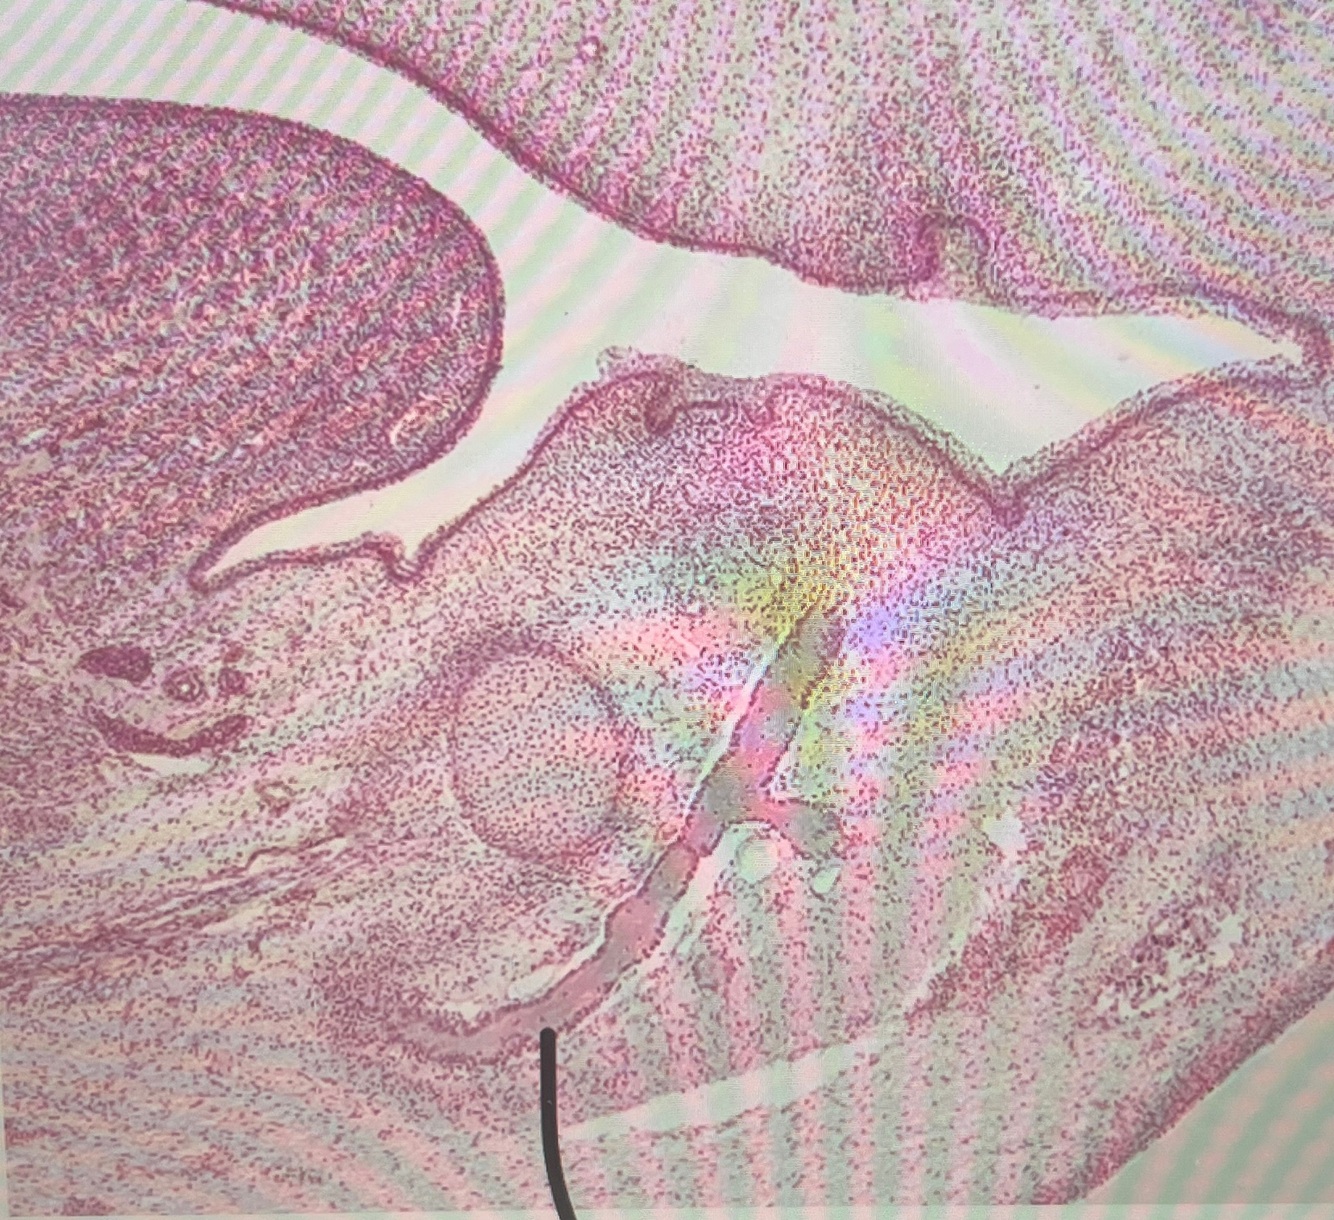

what is this structure?

A

nerve trunk

no nuclei in axons as they are in cell bodies that are miles away in the trigeminal ganglion, nuclei we do see are supporting cells

25

mandibular process

developing mandible

26

what is this structure at the base of the nasal capsule?

developing vomer dark cells are osteoblasts making bone

look at this inferior alveolar nerve next to the developing mandible